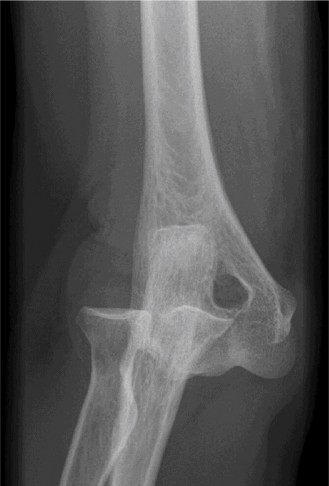

A 32-year-old male presented to the emergency department 1 hour after sustaining a fall while skateboarding. The patient complained of pain in the elbow with swelling and deformity present. He denied numbness or tingling.

Examination reveals deformity about the elbow with no open lesions or skin tenting. He has a palpable radial and ulnar pulse and is neurologically intact. His images are shown (Figs. 2–85 to 2–88).

Figure 2–86

The correct answer is (B). This is the most common type of elbow dislocation, and often does not cause any osseous injury. Posterolateral and posteromedial dislocation account for approximately 90% of dislocations. Adequate pre- and postreduction films are necessary to evaluate for fracture, which would change the classification to a complex injury.